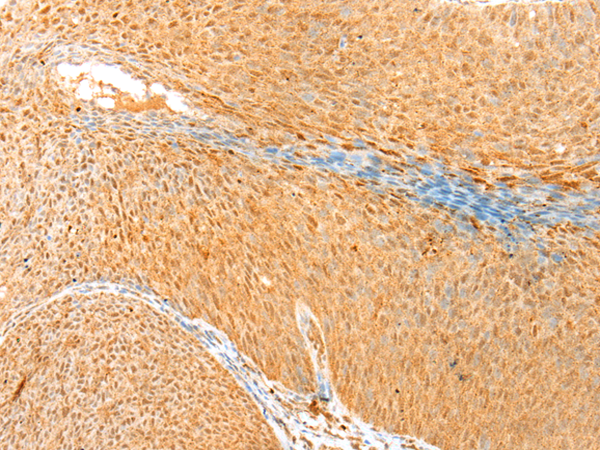

IHC positive control: |

Human cervical cancer and human tonsil |